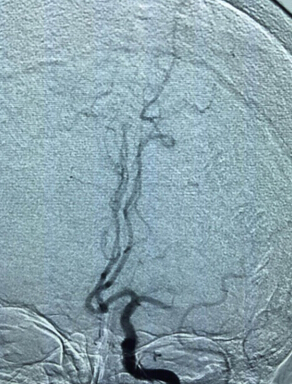

为了捕捉到造成老人险情的“罪魁祸首”——血栓,股动脉穿刺成功后,神经内科专家团队立即对老人左侧颈动脉及颈内动脉造影,发现患者左侧大脑中动脉中段闭塞,从造影图像来看,原本树状的脑内动脉血管左侧的“树枝”已经完全看不见了,血栓就在此处。

血管造影显示老人左侧脑颈内动脉管栓塞